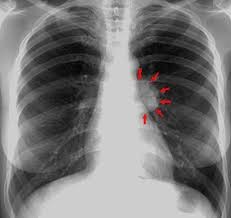

Paciente masculino de 23 años quien es llevado a consulta por productiva, malestar general fatiga y

disnea. Menciona además que últimamente ha tenido que utilizar más veces al día

su tratamiento de rescate para asma. Entre los antecedentes menciona que cree

que la Pachamama es perfecta, así que se come todas las verduras tal cual las

recoge de la siembra sin lavarla ni hervirla. Además, menciona tener malestar

abdominal, dolores tipo cólico, náuseas, meteorismo, vómitos ocasionales y

diarrea. Se le realiza un examen de heces que menciona que tiene

"huevos" y una biopsia pulmonar que verán a continuación... Con base

a toda la información... ¿Cuál de las siguientes radiografías torácicas es más

probable que tenga este paciente?